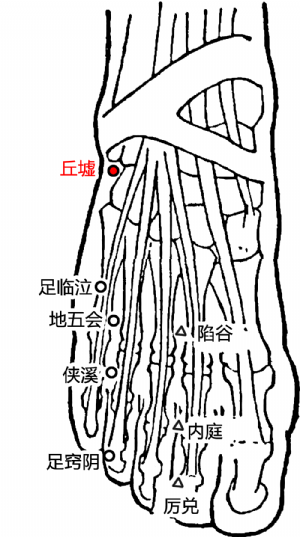

8 丘墟穴的定位

標準定位:丘墟穴在足外踝的前下方,當趾長伸肌腱的外側凹陷處。足少陽膽經的原穴[5]。

丘墟穴位於足外踝前下方,當趾長伸肌腱的外側凹陷處。伸足取之[5]。

丘墟穴位於足背外側,外踝前下緣,當趾長伸肌腱外側凹陷處[5]。

9 丘墟穴的取法

正坐垂足着地或側臥位,在外踝前下方,當趾長伸肌腱的外側凹陷處取穴。

丘墟穴位於足外踝前下方,當趾長伸肌腱的外側凹陷處。伸足取之[5]。